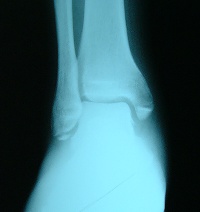

x-ray photo: Ando hospital

レントゲンを撮ってもらったところ、「あ、完全に折れてますね」だと。

脛骨先端、ようするにクルブシの先が両方ぽっきり折れている。